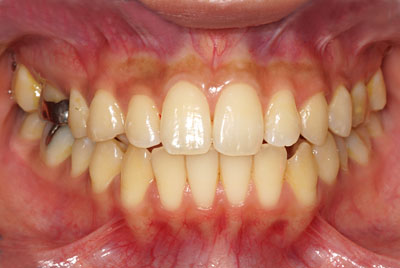

<img src="http://bz1.shinobi.jp/bin/ll?00004221F" border=0> December 01, 2012Sandy下稲荷嶽駒 BBSandy下稲荷嶽駒はBracket Bondingでした。まずはBB直前の様子です。正面から見た様子↓。12/01/12 本日 Bracket Bonging直前の様子↑上の歯の様子↓。12/01/12 本日 Bracket Bonging直前の様子↑下の歯の様子↓。12/01/12 本日 Bracket Bonging直前の様子↑虫歯も完全に治り神経の治療も完璧に終わり弱い歯はゴールドク...

さて、嶽駒(たけこま)シスターズの妹と言えばSandyなのですが今は姉のMiche同様、ホワイトニングの最中です。11/03/12 初診時の様子↑05/15/14 ホワイトニング2ヶ月目の本日の様子↑初診から558日、1年と193日が過ぎて福島に居た時は1日中寝ていた嶽駒(たけこま)シスターズは高山に昨年、二人で移り住んでからは徐々に健康が回復して今は週に何日かは外に出て自分の足で歩いてスーパーに行き買い物をするようになった。山崎先生の治療の指示にはほとんど従うこともなくヤクルト400も飲まない1日30分の散歩もしない早...